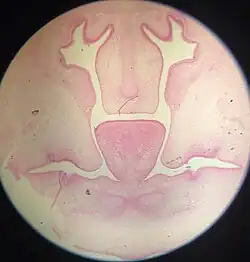

Frontal section of nasal cavities of a human embryo 28 mm. long (Kollmann) at about forty-four days. The two palatine processes can be seen here post-elevation in a horizontal position. The medial edges of the palatine processes are yet to fuse and form the roof of the oral cavity.